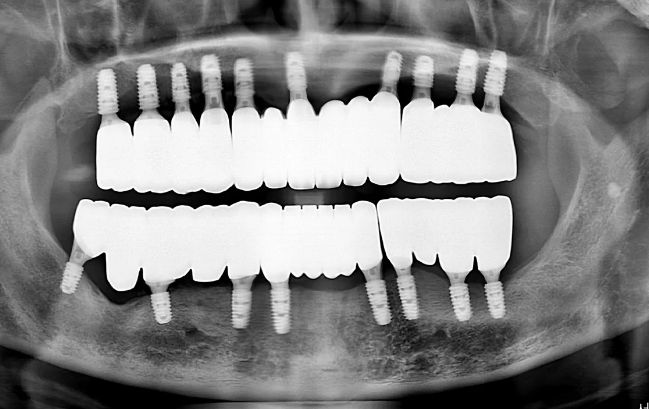

50대 남성, 원데이 수면 전체 임플란트 19개 식립